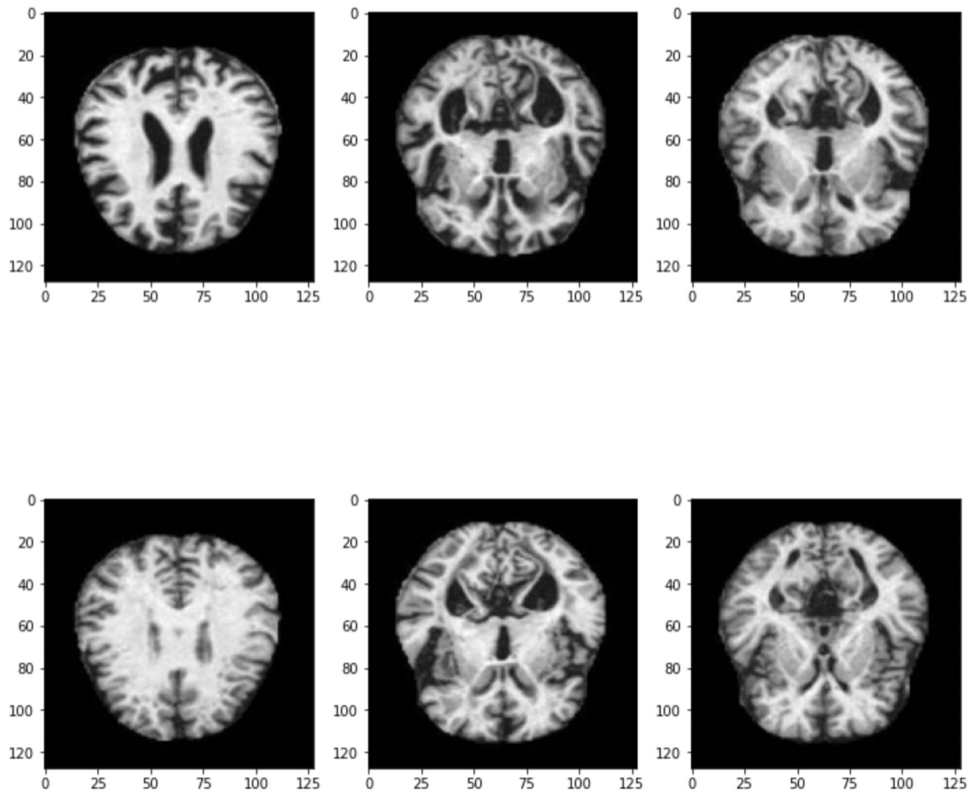

The dataset we used was found on Kaggle and consists of 6,400 MRI images (128 x 128), broken into 4 categories:

We conducted exploratory analysis on the dataset and found that the classes were imbalanced; meaning that we had more images of some classes versus others.